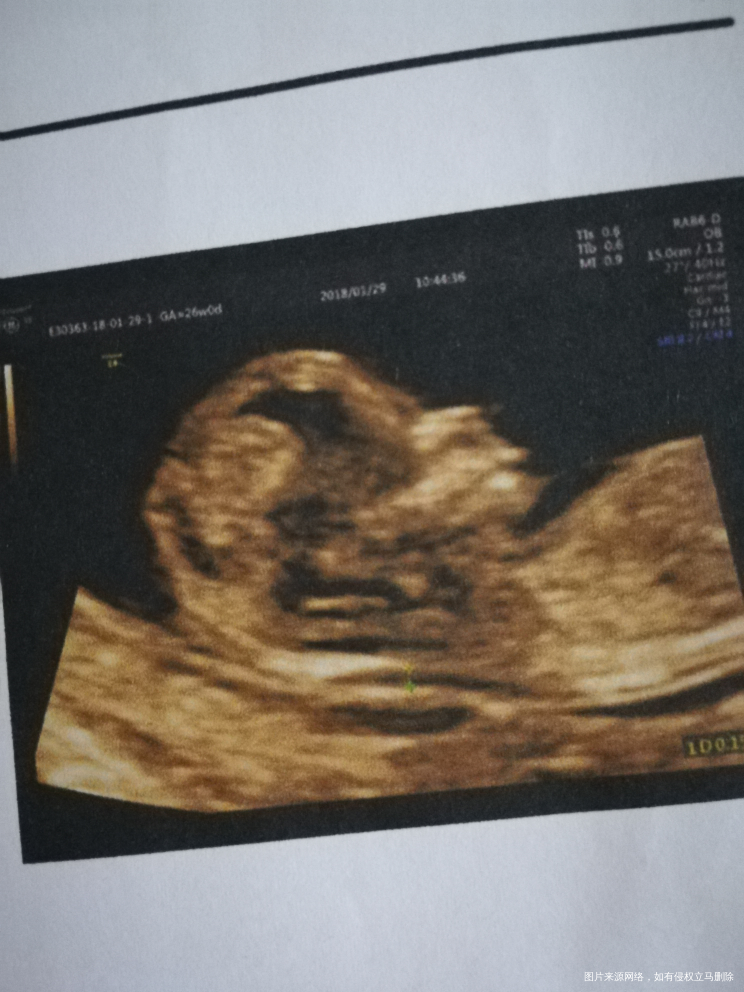

第一次宝宝趴着还倒立了医生照了几分钟推了好几下还是没翻过来只能过十分钟再来,第二次因为我上了个厕所回来等着的时候走来走去医生又说太活跃了😂😂感觉做了好久的样子医生也不多说什么害我心里还在想是不是有什么问题还是哪里不好。等医生说可以了的时候我看了一下电脑好几张都是仰躺着的样子也很清晰,心里不自觉的就软了下来。拿到结果一切正常再看看图片上的小人儿更是欢喜的不得了。愿后面的检查也一样顺利通过宝宝健康出生[鼓掌][鼓掌][鼓掌]还有姐妹们也都快快好孕![烧香][烧香]